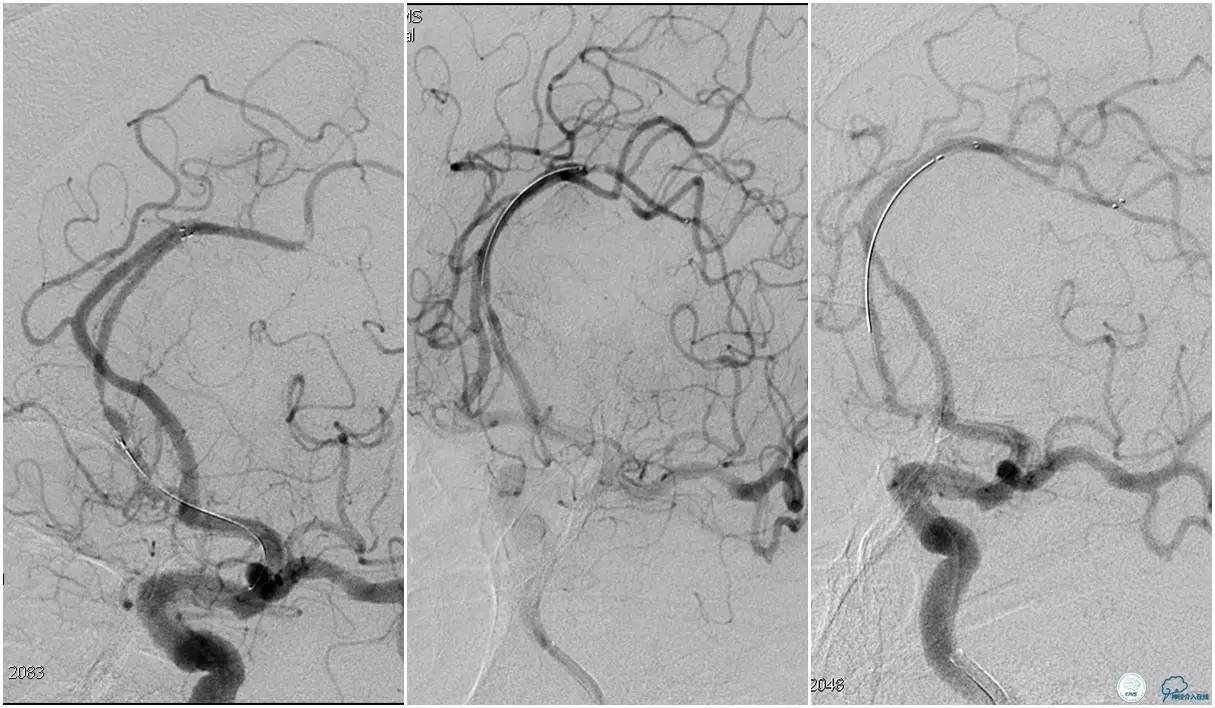

选用Solitaire-FR 4*20mm支架分别于右侧大脑前动脉A2-A3段,左侧胼周动脉,右侧胼周动脉取栓3次。

双侧大脑前动脉完全显影,TICI 3级,TOR 261min。